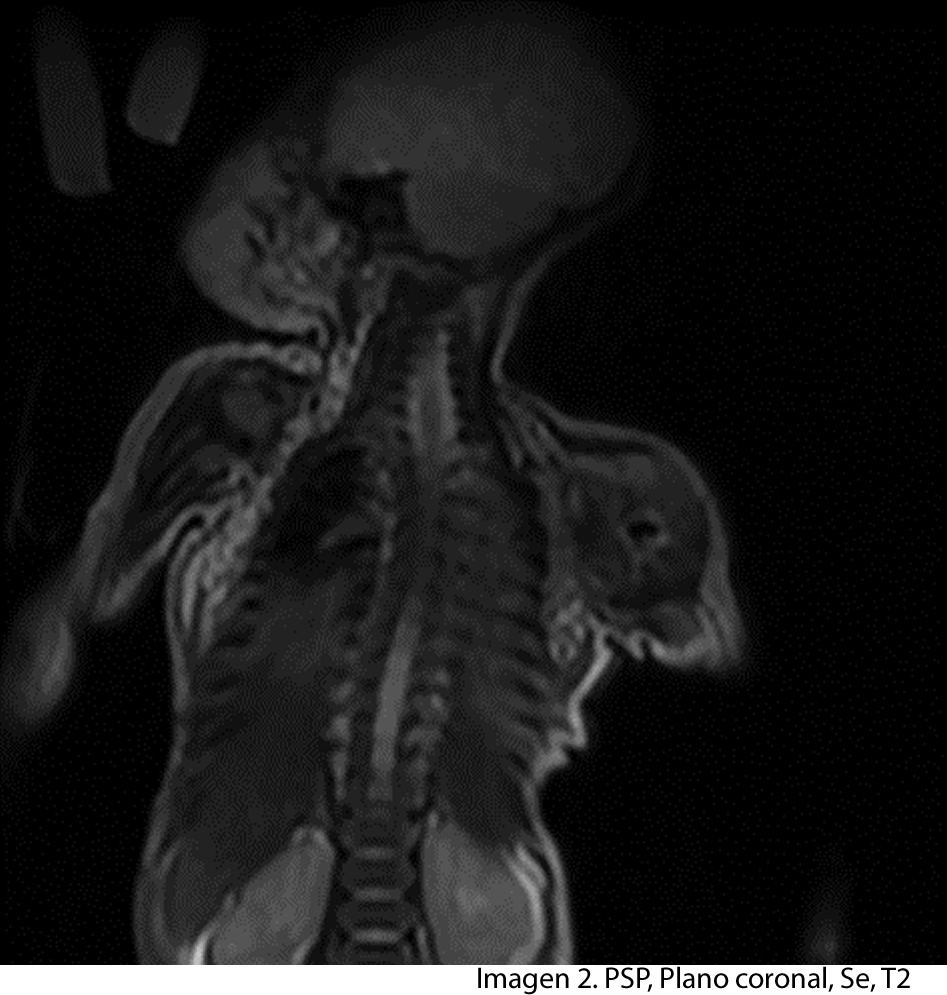

Paciente de 2 años de edad, madre refiere que después de un año de vida inicia con cambios de coloración y aumento de volumen en muslo izquierdo, seis meses después inicia a observar el mismo problema a nivel del hombro izquierdo, por lo que consulta a facultativo, el cual solicita estudio de resonancia de cuerpo entero, enfocado a muslo y hombro izquierdo.

Paciente nace en hospital nacional, sin ningún problema al momento del parto, madre no refiere problema durante el embarazo, indica que al año de vida inicia con aumento de volumen del muslo izquierdo, observa cambio de coloración en el mismo, seis meses después dichos cambios inician a observarse a nivel del hombro izquierdo. No refiere trauma alguno, ni enfermedad severa que lo afecte en los dos años de vida.

Se realiza estudio de resonancia magnética con un equipo de 1.5 tesla, se aplica protocolo de sedación, se utiliza bobina fase arrays, y se procede a adquirir un PSP, en tres planos, secuencias Se, ponderadas a T1 y T2, se administra medio de contraste por vía I.V.

A nivel del muslo izquierdo se observa una colección bilobulada, en la parte proximal se observa imagen que mide 7.05 x 7.17 cms en el tercio distal se observa imagen que mide 3 x 4.01 cms. En la ponderación T2 la lesión se vuelve hiperintensa y en la ponderación T1 con mdc la lesión se vuelve hipointensa con realce de la periferia, lo que confirma la presencia de absceso.

La diáfisis femoral proximal se ve totalmente destruida, a nivel del hombro izquierdo la cabeza del humero no se observa.